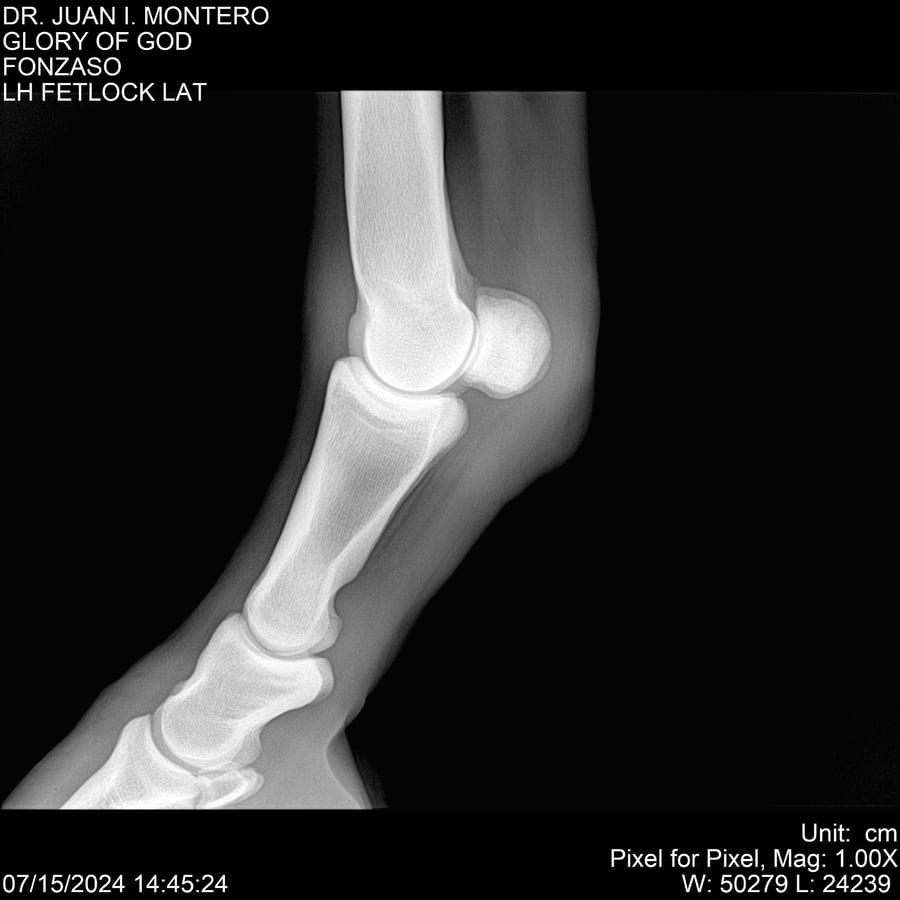

LOTE 10, GLORY OF GOD 🔥 🔥 🔥 Lote Anterior Volver al remate Lote Siguiente Ficha Contacto Montevideo - Ficha del Lote Identificador: #281389 Categoría: Yeguarizos Montevideo - 115 Visualizaciones ClicData Contacto Empresa: Abelenda N. R., Walter Hugo Nombre*: Teléfono* : E-mail* : Mensaje Enviar Registrese gratis Este contenido Exclusivo está disponible sólo para usuarios registrados Ingresar